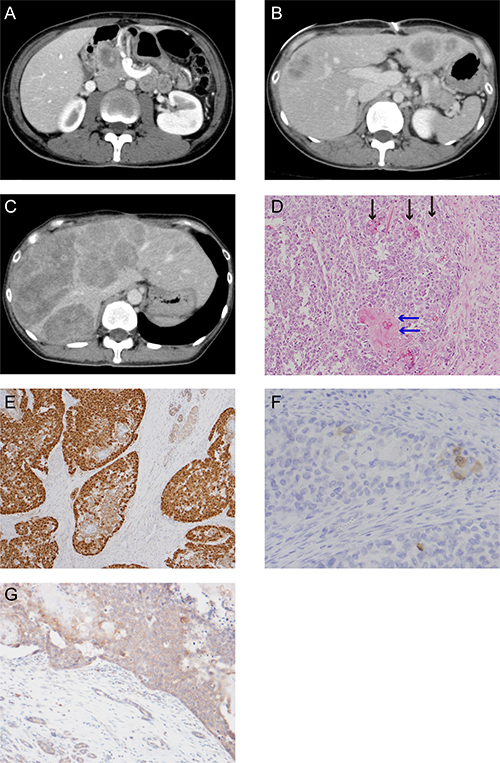

A 37-year-old woman visited our hospital complaining of abdominal pain. She had no past or familial history of neoplasms. A computed tomography (CT) scan showed a 5 cm abnormal mass in the pancreas head. She was suspected for pancreatoblastoma by CT-guided biopsy (Figure 1A) and was sent for a pancreaticoduodenectomy.

The postoperative pathological findings showed squamoid nests, some with keratinization (Figure 1D). Immunohistological analysis indicated an abnormal nuclear accumulation of β-catenin proteins and the expression of Bcl-10, a pancreatic acinar cell marker, in the tumor tissues (Figures 1E and 1F). A pathological diagnosis of pancreatoblastoma depends on its acinar differentiation and on the existence of squamoid nests; therefore, this tumor was finally diagnosed as pancreatoblastoma according to these findings.

Figure 1: CT scan images and histological appearance of this case. (A) CT scan image at first visit. (B) CT scan image at postsurgical recurrence of liver metastasis. (C) The last CT scan image before the patient died. (D) Hematoxylin and eosin staining (magnification, ×200). The black arrow shows the squamoid nest and the blue arrow shows the squamoid nest with keratinization. (E) Immunohistochemical staining for β-catenin (magnification, ×100). (F) Scattered tumor cell shows positive for Bcl-10 (magnification, ×200). (G) Immunohistochemical staining for APC (magnification, ×50).

A CT scan taken three months postoperatively showed metastatic recurrence in the liver (Figure 1B). She received one course of adriamycin and gemcitabine chemotherapy, with no response. We treated her with cisplatin and S-1 as a second line chemotherapy. Although the tumor temporarily exhibited no change in size, after six cycles of cisplatin and S-1 chemotherapy her liver metastatic pancreatoblastoma increased in size (Figure 1C). We were unable to achieve any response via salvage treatment, and she ultimately died of pancreatoblastoma progression 13 months after diagnosis.

We conducted genetic analysis to investigate genetic alterations in the tumor using a cancer panel (OncoDEEP®, Supplementary Table 1). We identified a previously unreported missense APC mutation of c.5503A > G (p.R1835G). We also confirmed the mutation of the APC gene by Sanger sequencing (Figure 2A) and the expression of APC protein by immunohistochemical staining (Figure 1G) in tumor tissue samples from the patient. Allele frequency of this mutated allele was 99% in the cancer panel analysis. In addition, we did not find any other alterations of the genes involving the Wnt signal pathway, including CTNNB1. After obtaining written informed consent from the patient, we analyzed her germ line APC gene from her saliva and found a heterogeneous mutation in the 1835 codon of the APC gene (Figure 2A). These data suggest that a LOH of the APC gene occurred in the tumor, and the products of the APC missense mutation took part in tumorigenesis.